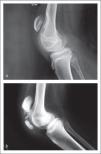

Otro factor que participa en el desarrollo de la marcha agazapada es la co-contracción entre músculos agonistas y antagonistas (1) que presentan los pacientes con parálisis cerebral. Éstos al intentar extender sus rodillas para mantenerse erguidos, contraen los músculos extensores de rodilla y simultáneamente en forma involuntaria, contraen también los músculos flexores de esa articulación. Este sobre esfuerzo tiene como resultado una elongación anormal del tendón rotuliano, lo que produce una patela alta. En ocasiones se pueden manifestar fracturas por estrés de las patelas (Figura 4), lo que finalmente aumenta aún más la flexión irreductible de sus rodillas, ya que estas fracturas son sub-diagnosticadas y habitualmente no se tratan. La manifestación más grave de este proceso de agazapamiento puede incluso producir la pérdida de la marcha en pacientes mayores (5) y constituye la historia natural de la enfermedad en muchos casos severos (6).

Falla extensión de rodilla

a) En la figura superior se observa la rodilla de un paciente con sobre elongación del tendón rotuliano que genera una patela alta severa con depresión en el fémur distal.

b) En la figura inferior se observa una fractura por estrés de la patela secundaria a co-contracción muscular entre agonistas y antagonistas en una rodilla de un paciente con parálisis cerebral.